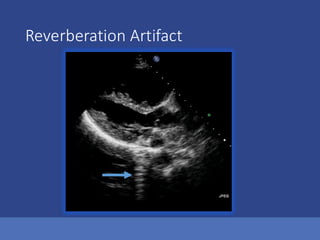

Reverberation Artifact

Ultrasound Assumption Violations Anotherway to think about these Axial Direction Artifacts located below the real Structure Lateral Direction Artifacts located to the side of the real Structure 1.Reverberations 2.Mirror Image Artifacts 3.Acoustical shadowing or enhancement 1.Beam Width Artifacts 2.Side Lobe Artifacts 3.Refraction Artifacts